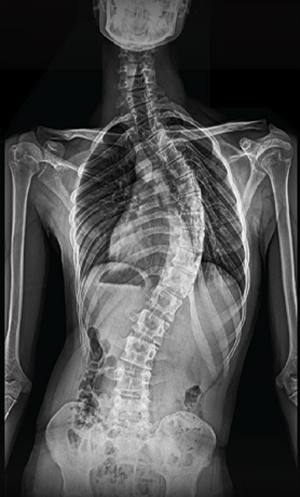

BEYOND RECOVERY : REAL STORIES

Gallery : Before - After